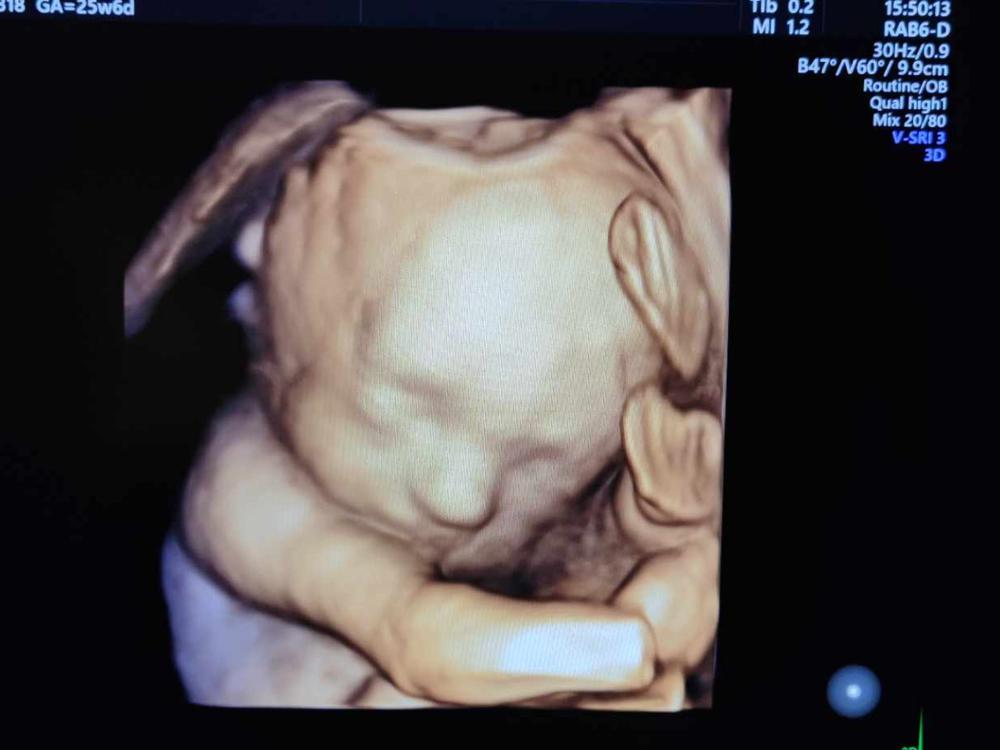

Sam and Simone Hight lost their baby boy, Gideon, 26 weeks into the pregnancy. They and their six other children were able to hold him and say goodbye after his lifeless body was delivered by Simone.

It has been a hard road for the Hight family, with a diagnosis for their baby of Trisomy 18. The accompanying physical abnormalities meant he was statistically unlikely to survive to birth, yet Sam and Simone chose to uphold their belief that this little life was made in God’s image and needed to be preserved as long as possible.